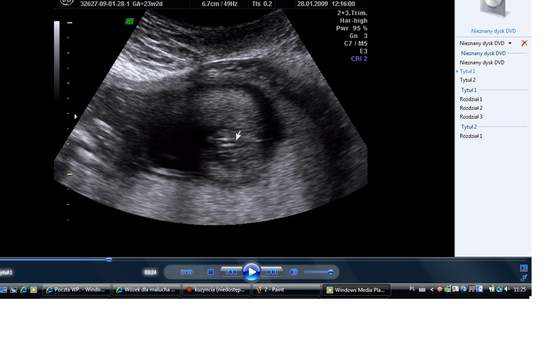

3 d?najwazniejsze badanieJa zamierzam zrobić to badanie, żeby upewnić się że wszystko z Dzidzią jest dobrze. To badanie pozwala upewnić się czy nie występują u Dziecka żadne wady. Na jednym badaniu już byłam, ale to jest 2D w 13 albo 14 tygodniu. Widziałam jak Dziecko się rusza wręcz można było zobaczyć jak szaleje ruszało się we wszystkie strony aż lekarz się śmiał. Chwile przerwy Dziecko sobie zrobiło jak chciało się po "nosku podrapać". Mamy zdjęcia. Codziennie jak wstaje patrze na nie.Powiedział nam też że będzie chłopiec, ale wydaje mi się że tak wcześnie nie da się tego określić. Mąż się cieszy a ja i tak wiem że będzie dziewczynka

. Wydaje mi się że badanie 3D jest jedno z ważniejszych badań w ciąży.